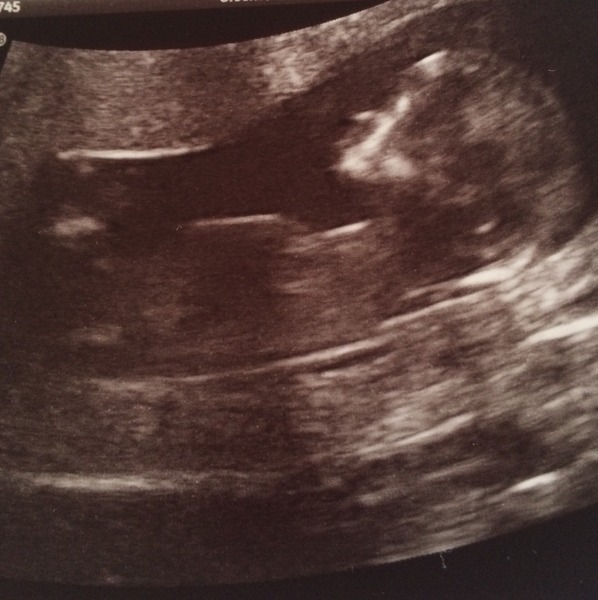

KatoPotato · 03/11/2014 16:51

Here's a better version! But yes, lots of squirming had to jump up and down a lot, and was sent for walks and drinks and wees. Sonographer was determined and lovely!

Kato that is a terrific pic! Congratulations! And very well done to your tenacious sonographer. Smile

Yay for a lovely scan Kato Smile

There's another from the front but it looks like a spooky Halloween pic, complete with little clawing hand!

Awwww kato that is lovely :) congratulations!

Good news on the scan Kato!

Great scan photo Kato, glad it all went well. Did you have a little tear or was it all smiles?